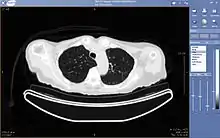

A chest image displayed via a PACS